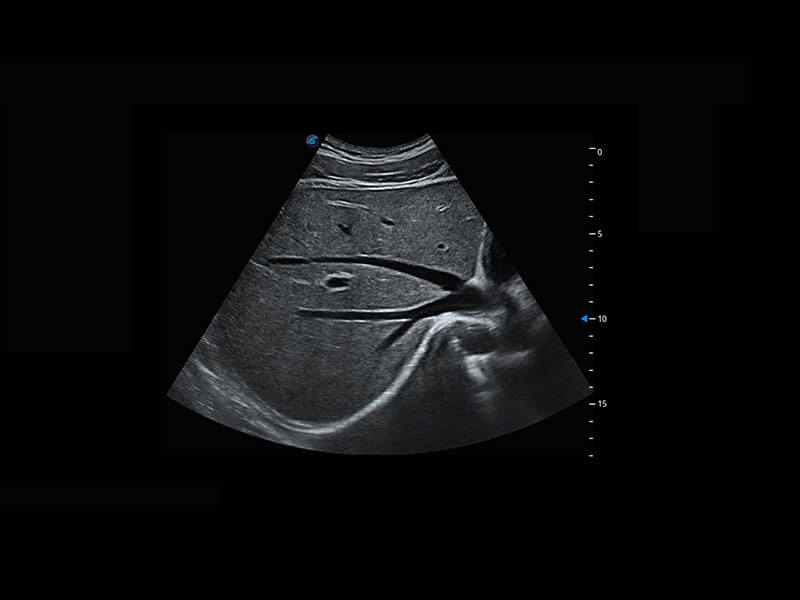

新生儿肝血管癌

新生儿脊髓圆锥

新生儿心脏